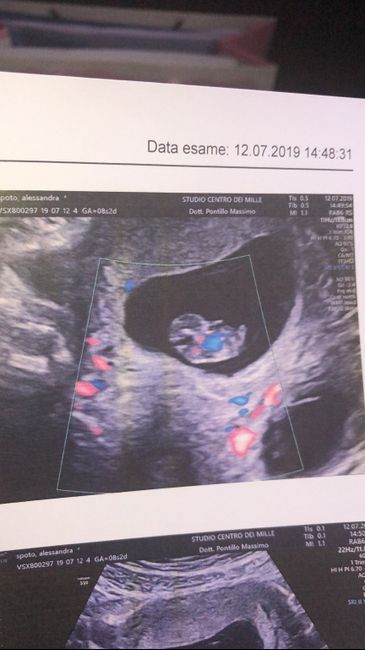

Ragazze secondo il metodo Ramzi con questa eco interna fatta a 7+4 cosa sarebbe? Maschietto o femminuccia? https://ibb.co/sbbw7yw https://ibb.co/vmyfywyb

Ragazze ciao ho fatto l’eco a 8+4 secondo voi è maschio o femmina?

Metodo Ramzi 2